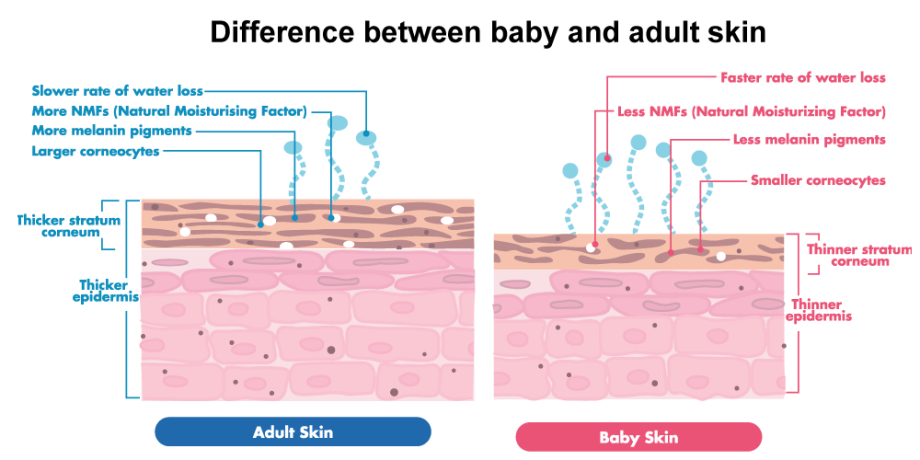

Your baby’s skin is different from adult skin and continues to develop over the first year of life. The baby’s skin is 30% thinner compared to adult skin.

Besides being less mature, the baby’s skin loses water faster, is more vulnerable to the environment and more sensitive to sunlight. The structure of the baby’s skin makes it more prone to irritation, infection and allergies compared to adults.